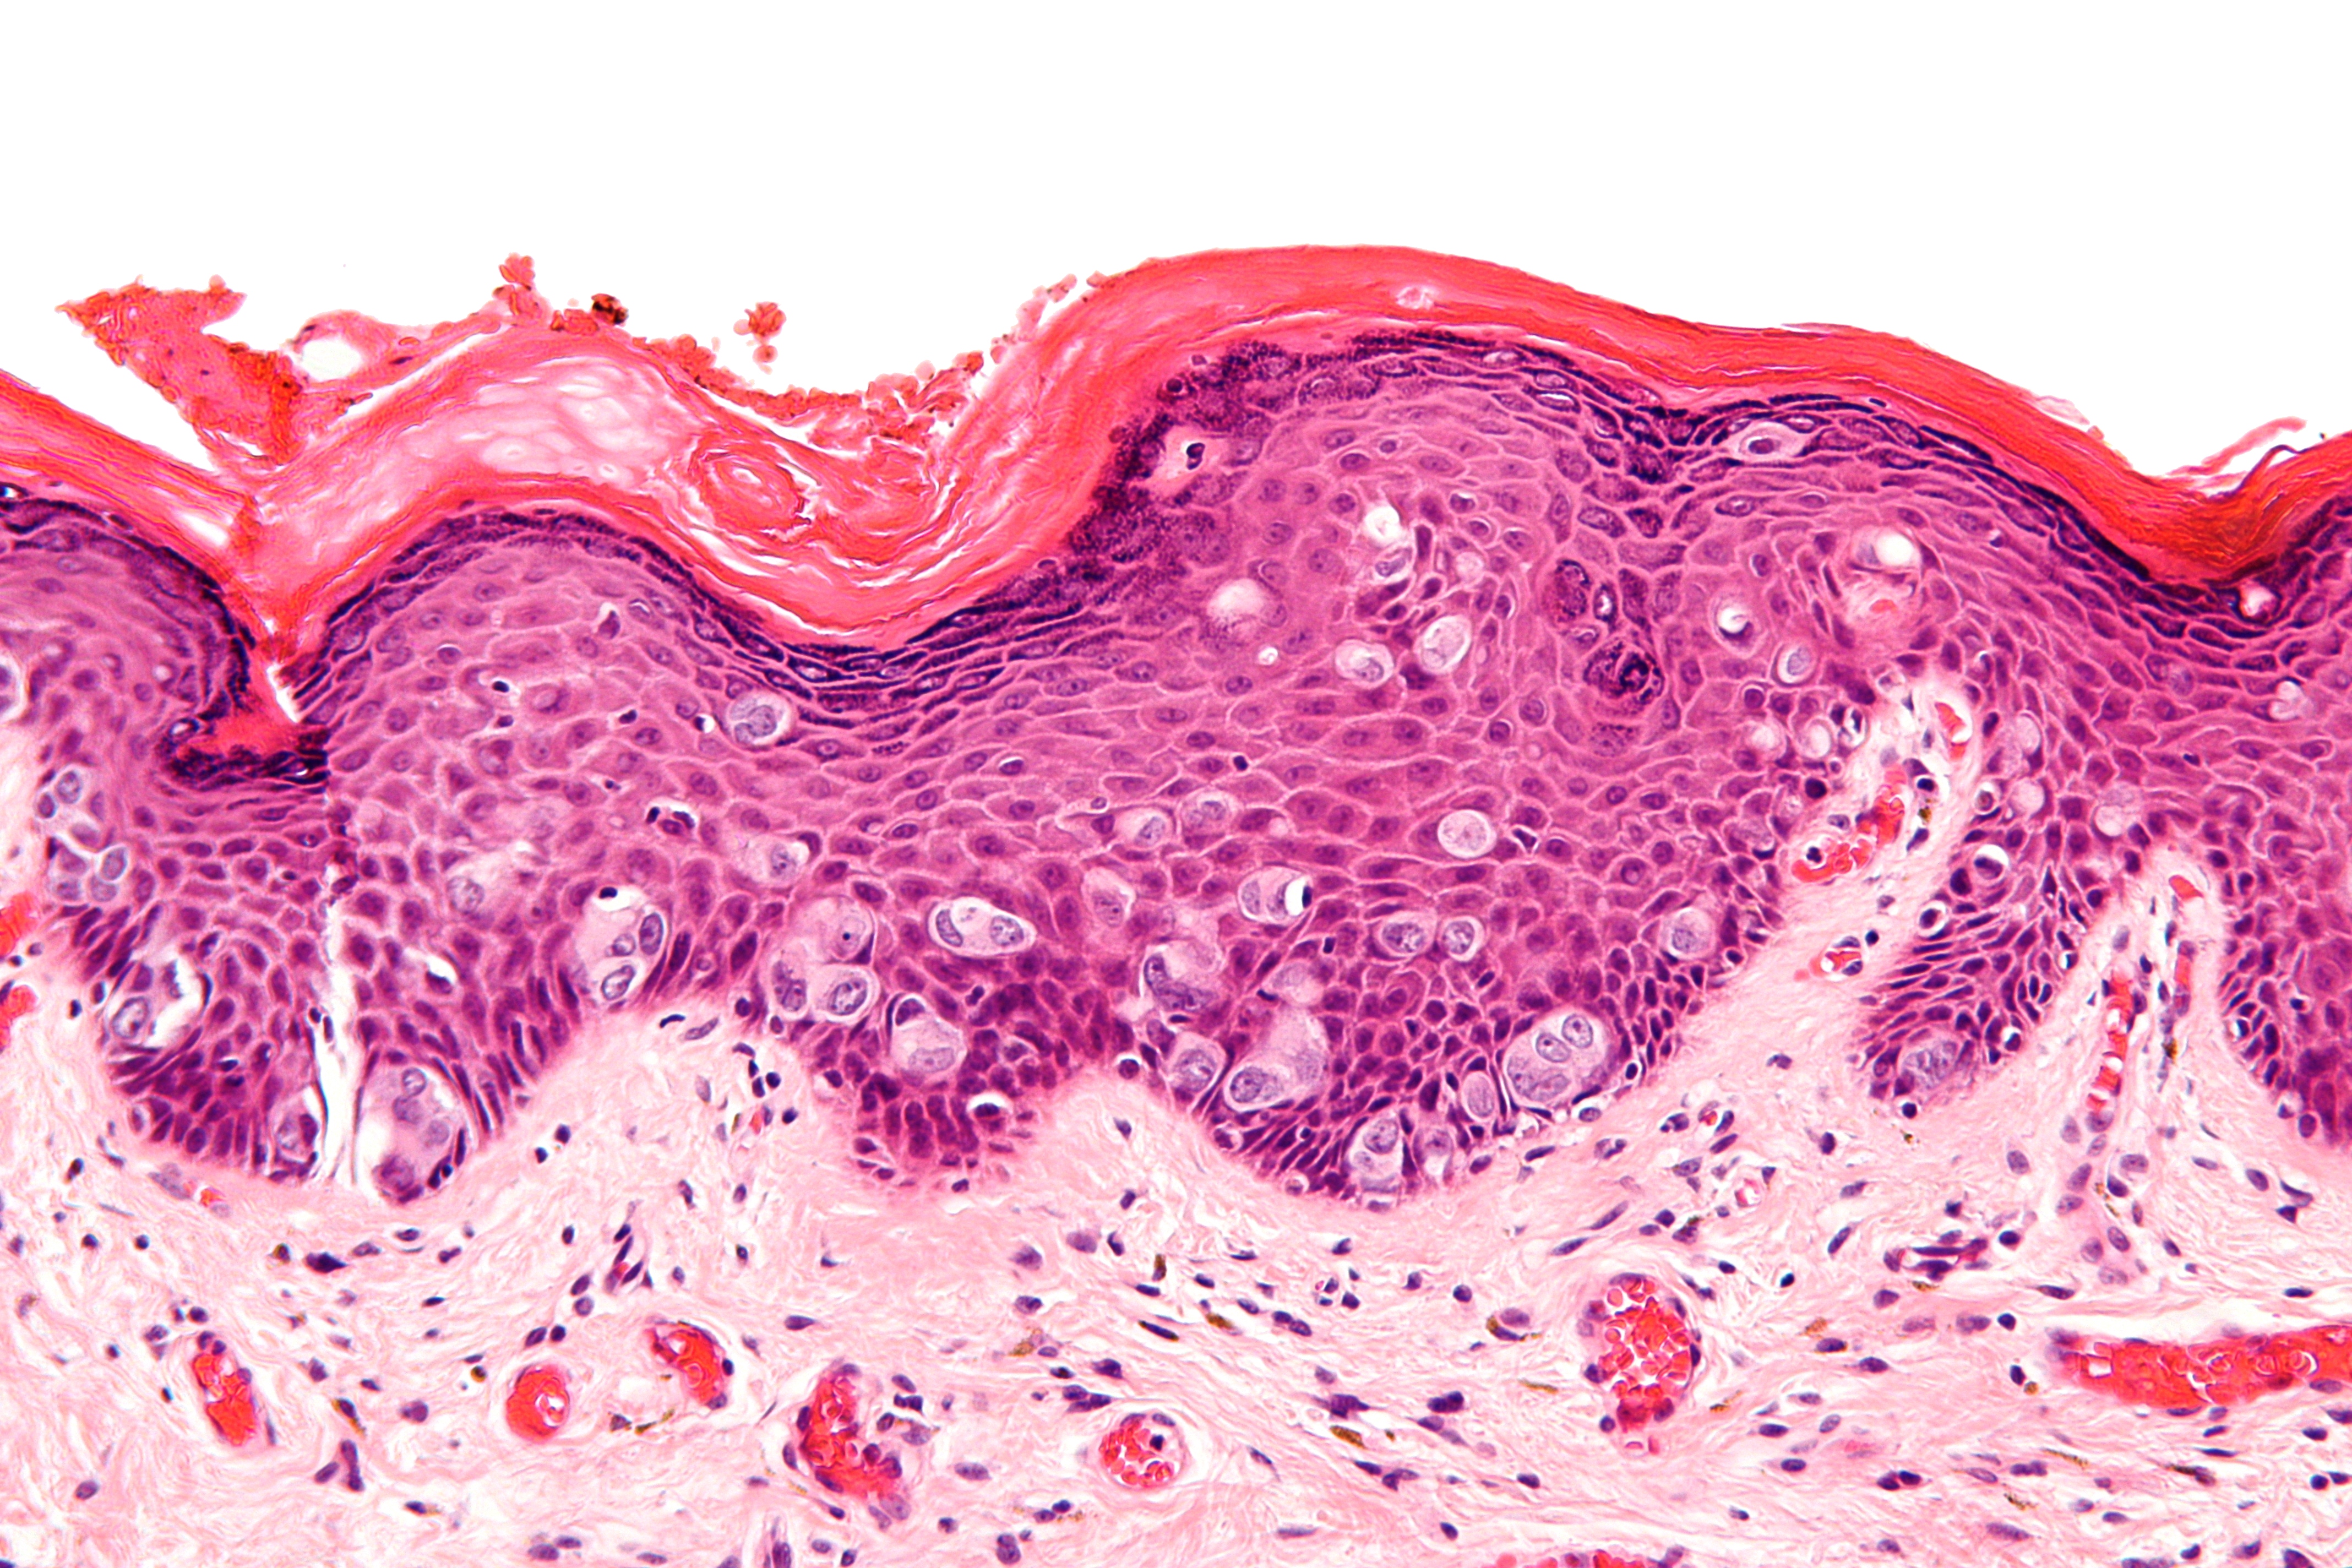

- Distinct patterns of tumor formation. Some tumors can form unique arrangements within themselves, like whirling patterns or rosettes (see the header image for this blog as an example). Sometimes these patterns can also form around blood vessels, especially since actively growing tumors need considerable blood supply.

- Invasion. Tissues are divided into layers and nuclei, each of which usually show distinct boundaries between different cell types. When one cell type crosses that boundary into another, that can be indicative of malignancy (see image below).

In this image you can see a clear indication of an invasive cancer, in which you see large cells invading the epidermis of the skin of the breast. This is taken from a patient with Extramammary Paget’s Disease. Image borrowed from here.